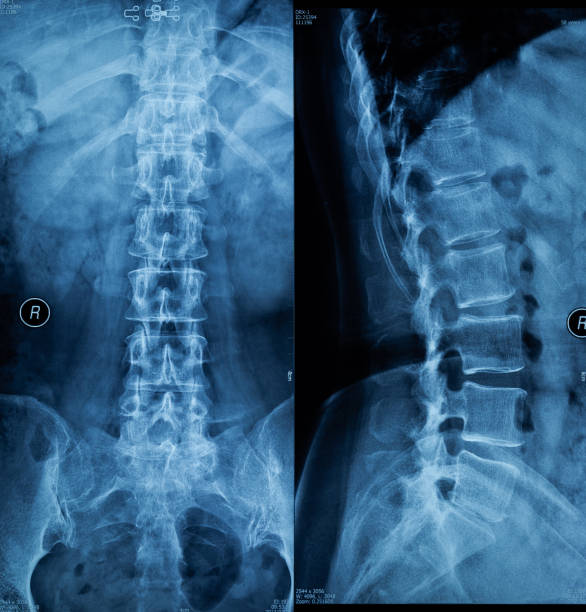

Рентген поясницы: анатомические особенности и медицинские исследования